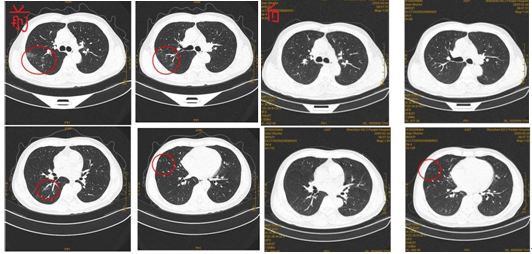

以下为排除"一切肺炎"临床工作的缩影: